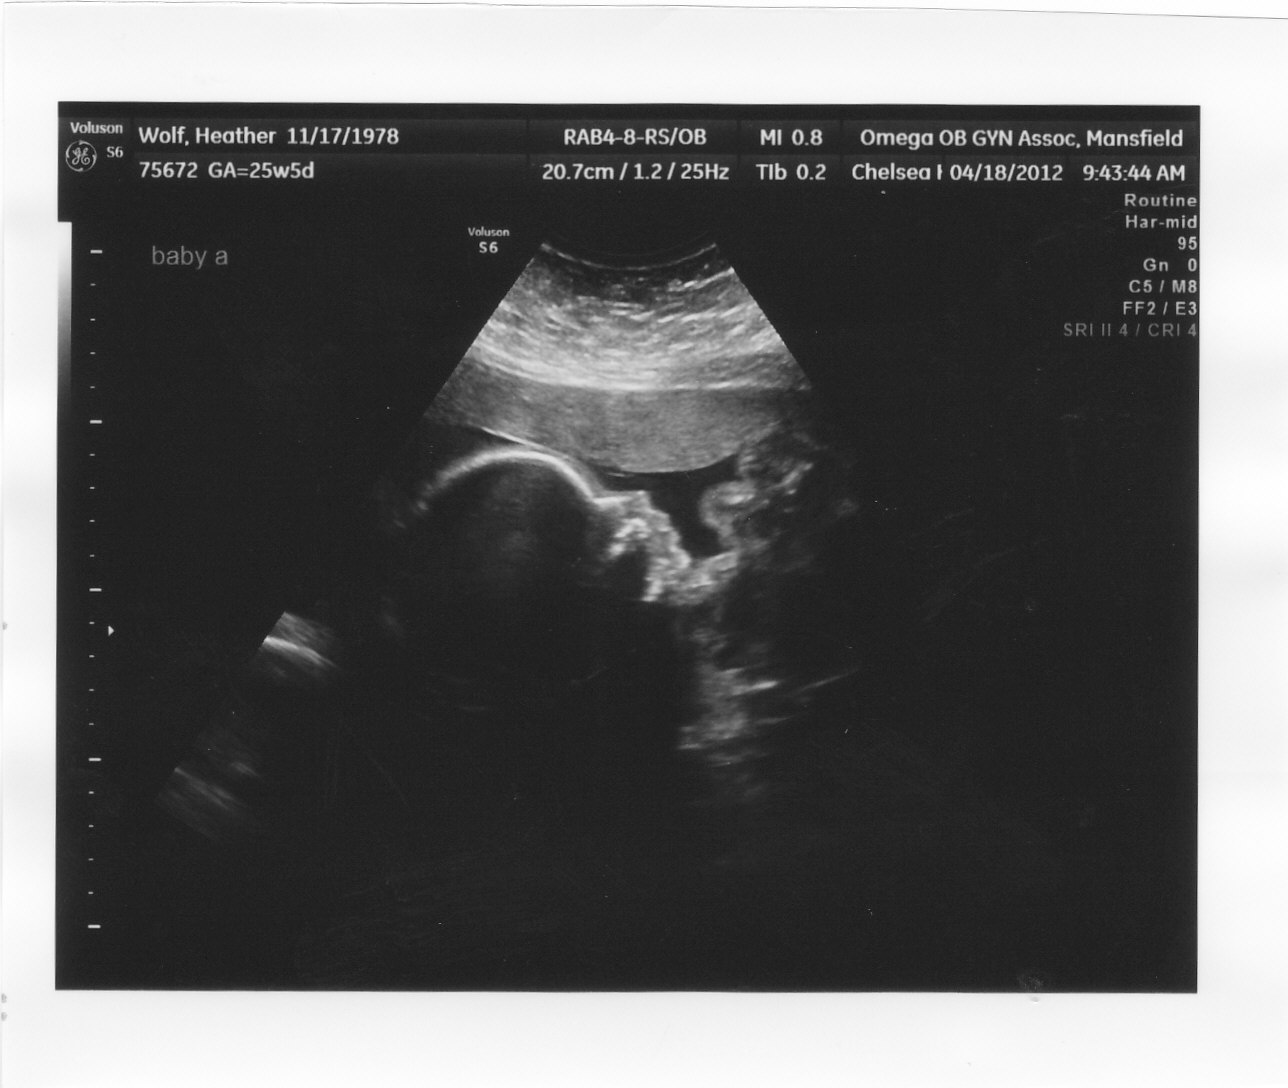

| Here they are sharing secrets . . . or conniving already |